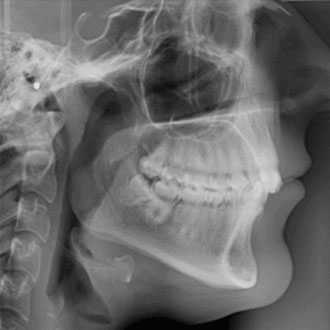

Cephalometric radiography provides a complete view of the dento-maxillo facial region. The functionally designed and easy to use head positioner ensures accurate patient positioning in lateral a.p and p.a technique.